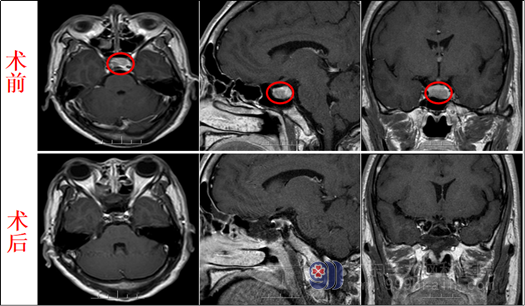

患者术前术后MR:

为明确病因,徐阿姨在我院完成了相关检查,影像检查结果示:蝶鞍扩大,鞍内偏底部示范围约18×13× 10mm的团块状不均匀等、稍长T1等、稍长12异常信号,增强后可见不均匀强化,鞍底下陷,视交叉及垂体柄未见受压,邻近双侧颈内动脉未见包绕(Knosp0级):垂体后叶区小囊状无强化影;脑室系统未见扩张,脑沟、脑裂及脑池未见增宽,中线结构居中。鼻旁窦粘膜稍增厚,右侧筛窦囊状不均匀长T2信号。诊断结果:1.鞍内偏底部占位性病变,考虑垂体腺瘤;2.垂体后叶区小囊样信号影考虑Rathke,s囊肿;3.松果体小囊肿;4.鼻旁窦炎症,伴右侧后组筛窦小囊肿。